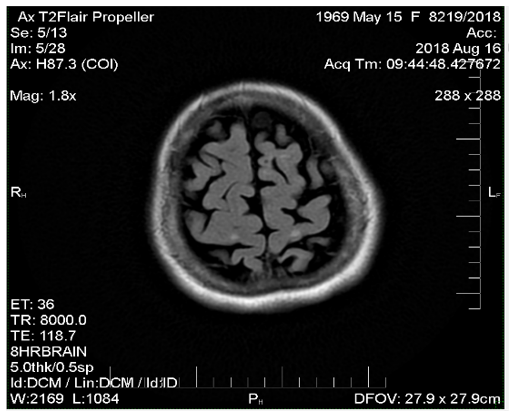

Comparing magnetic resonance recordings over time, it was determined that within a 10-year period, practically no new lesions had formed (Figure 1-3). Although the patient continues to experience some neurological interference, she remains active, fully functional, and independent. She travels frequently, has purchased a car, and drives herself. Her current neurological condition is characterized as mild paraparesis affecting the lower extremities and the right arm, yet she maintains mobility and autonomy. This review sufficiently covers her progress; no additional remarks are necessary. Conclusion stands on its own.

Figure 2 MRI image from 2018.

Figure 3 MRI images from 2020 show that there are no new lesions.